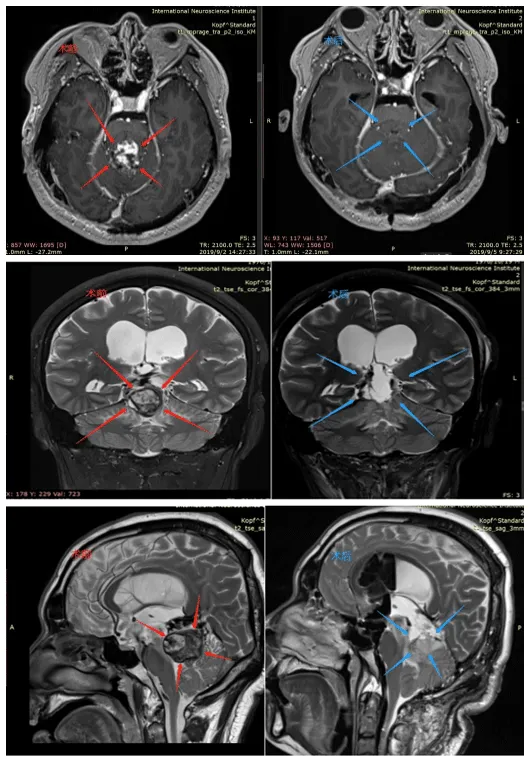

一次看似平常的摔跤,对活泼好动的孩子来说本是常事。但对于6岁的鑫鑫而言,一次意外摔破头皮后的检查,却揭开了更严峻的真相他的大脑中心,松果体区,潜藏着一个不断长大的肿瘤。 临...

Tank!病房中,一位6岁男孩的欢呼预示着生命的重启。这是他开颅术后的第二天,而这一天,全家人足足等了2年。 01 意外发现的松果体区占位 Pineal region tumor 2021年,6岁男孩鑫鑫因意外摔伤头皮...

六岁的鑫鑫,因在幼儿园意外摔伤头皮就诊,CT检查意外捕捉到松果体区阴影与局部钙化灶;进一步MRI精查,一枚221417mm的占位病变随之浮出水面。 三十六岁的晴晴,不过是因鼻炎顺带行颅脑...